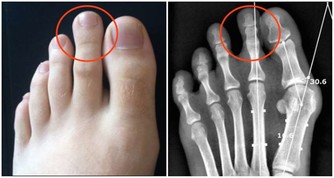

1、盆腔炎

盆腔炎是指發生在盆腔生殖器官、盆腔腹膜和周圍結締組織的炎症。若急性盆腔炎沒有得到有效治療會轉化成慢性的,發病時間長且病情頑固。期間要注意個人衛生,防止細菌逆行。